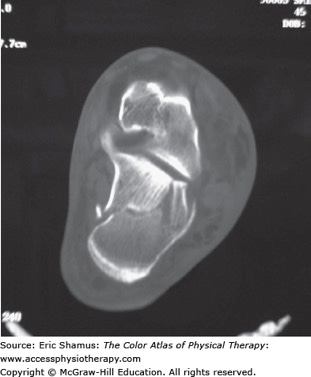

Axial CT section showing a fracture of the calcaneus caused by an axial loading mechanism. (From Doherty GM. Current Diagnosis & Treatment: Surgery. 13th ed. http://www.accessmedicine.com. Copyright © The McGraw-Hill Companies, Inc. All rights reserved.)

Other important imaging includes CT scans for more detail, and bone scans if the fracture appears to be a stress fracture.